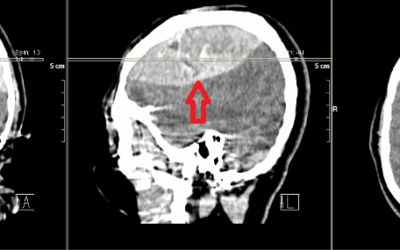

Hipofiz tümörlerinin teşhisi, detaylı klinik değerlendirme ve görüntüleme yöntemleriyle konur:

- MRG (Manyetik Rezonans Görüntüleme): Hipofiz bezindeki tümörlerin detaylı olarak görüntülenmesini sağlar.